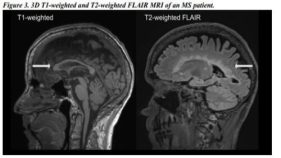

医療・健康 多発性硬化症における神経変性の定量的MRIバイオマーカー(Quantitative MRI Biomarkers of Neurodegeneration in Multiple Sclerosis)